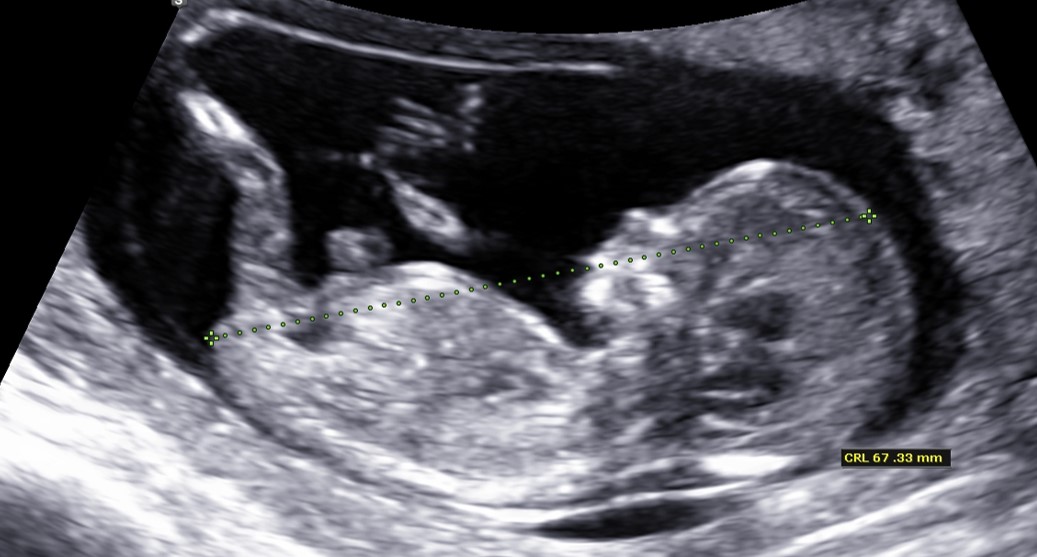

Lopullinen laskettu aika määritetään ensimmäisen ultraäänitutkimuksen yhteydessä. Määritys perustuu sikiön pää-perämittaan.

Yhdistelmäseulonta sisältää ultraäänitutkimuksen ja äidin verinäytteen. Verinäytteestä määritetään istukka- ja sikiöperäisiä hormoni- ja valkuaisainepitoisuuksia. Ultraäänitutkimuksessa mitataan sikiön niskaturvotuksen lisäksi sikiön pää-perämitta. Riskiarvioon vaikuttaa myös äidin ikä. Verinäyte otetaan äidiltä ennen ultraäänitutkimusta raskausviikoilla 9+0–11+6 ja ultraäänitutkimus tehdään raskausviikoilla 11+0–13+6. Paras ajankohta käydä laboratoriossa on, kun on täynnä 10 raskausviikkoa.